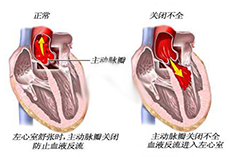

心脏瓣膜病及其他疾病

疾病介绍:心脏瓣膜病及其他疾病心脏瓣膜病就是指二尖瓣、三尖瓣、主动脉瓣和肺动脉瓣的瓣膜因风湿热、黏液变性、退行性改变、先天性畸形、缺血性坏死、感染或创…【详细】

心脏瓣膜病及其他疾病

疾病介绍:心脏瓣膜病及其他疾病心脏瓣膜病就是指二尖瓣、三尖瓣、主动脉瓣和肺动脉瓣的瓣膜因风湿热、黏液变性、退行性改变、先天性畸形、缺血性坏死、感染或创…【详细】

心脏瓣膜病及其他疾病

疾病介绍:心脏瓣膜病及其他疾病心脏瓣膜病就是指二尖瓣、三尖瓣、主动脉瓣和肺动脉瓣的瓣膜因风湿热、黏液变性、退行性改变、先天性畸形、缺血性坏死、感染或创…【详细】

心脏瓣膜病及其他疾病

疾病介绍:心脏瓣膜病及其他疾病心脏瓣膜病就是指二尖瓣、三尖瓣、主动脉瓣和肺动脉瓣的瓣膜因风湿热、黏液变性、退行性改变、先天性畸形、缺血性坏死、感染或创…【详细】

心脏瓣膜病及其他疾病

疾病介绍:心脏瓣膜病及其他疾病心脏瓣膜病就是指二尖瓣、三尖瓣、主动脉瓣和肺动脉瓣的瓣膜因风湿热、黏液变性、退行性改变、先天性畸形、缺血性坏死、感染或创…【详细】

心脏瓣膜病及其他疾病

疾病介绍:心脏瓣膜病及其他疾病心脏瓣膜病就是指二尖瓣、三尖瓣、主动脉瓣和肺动脉瓣的瓣膜因风湿热、黏液变性、退行性改变、先天性畸形、缺血性坏死、感染或创…【详细】

心脏瓣膜病及其他疾病

疾病介绍:心脏瓣膜病及其他疾病心脏瓣膜病就是指二尖瓣、三尖瓣、主动脉瓣和肺动脉瓣的瓣膜因风湿热、黏液变性、退行性改变、先天性畸形、缺血性坏死、感染或创…【详细】